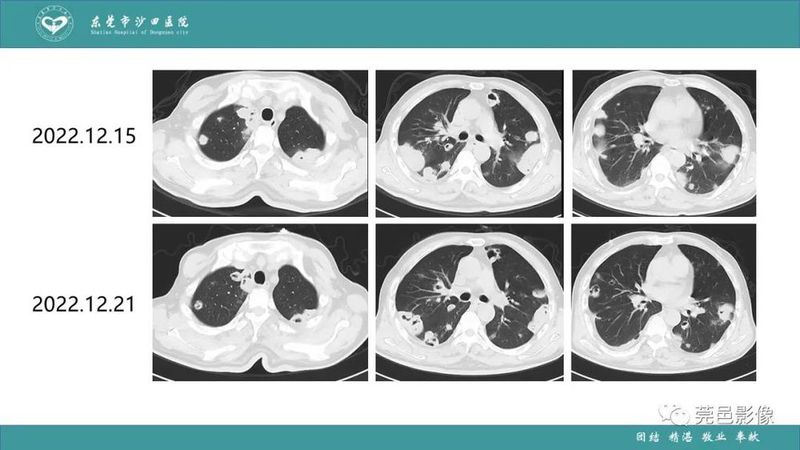

「肺炎克雷伯杆菌肺炎」影像学诊断+鉴别诊断